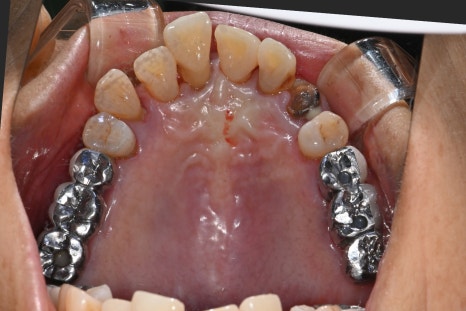

이번 환자분은 65세 여성으로

위 앞니가 여러 개 상실된 상태로 내원하셨습니다.

발치와 동시에 진행된 임플란트 식립

이번 케이스에서는

손상된 앞니를 발치한 후

임플란트 식립이 동시에 진행되었습니다.

✔ 전치부 다수 임플란트 식립

✔ 골유도재생술(GBR) 진행

✔ 동종골 이식 병행

앞니는 뼈가 얇기 때문에

뼈이식

이 함께 진행되는 경우가 많습니다.